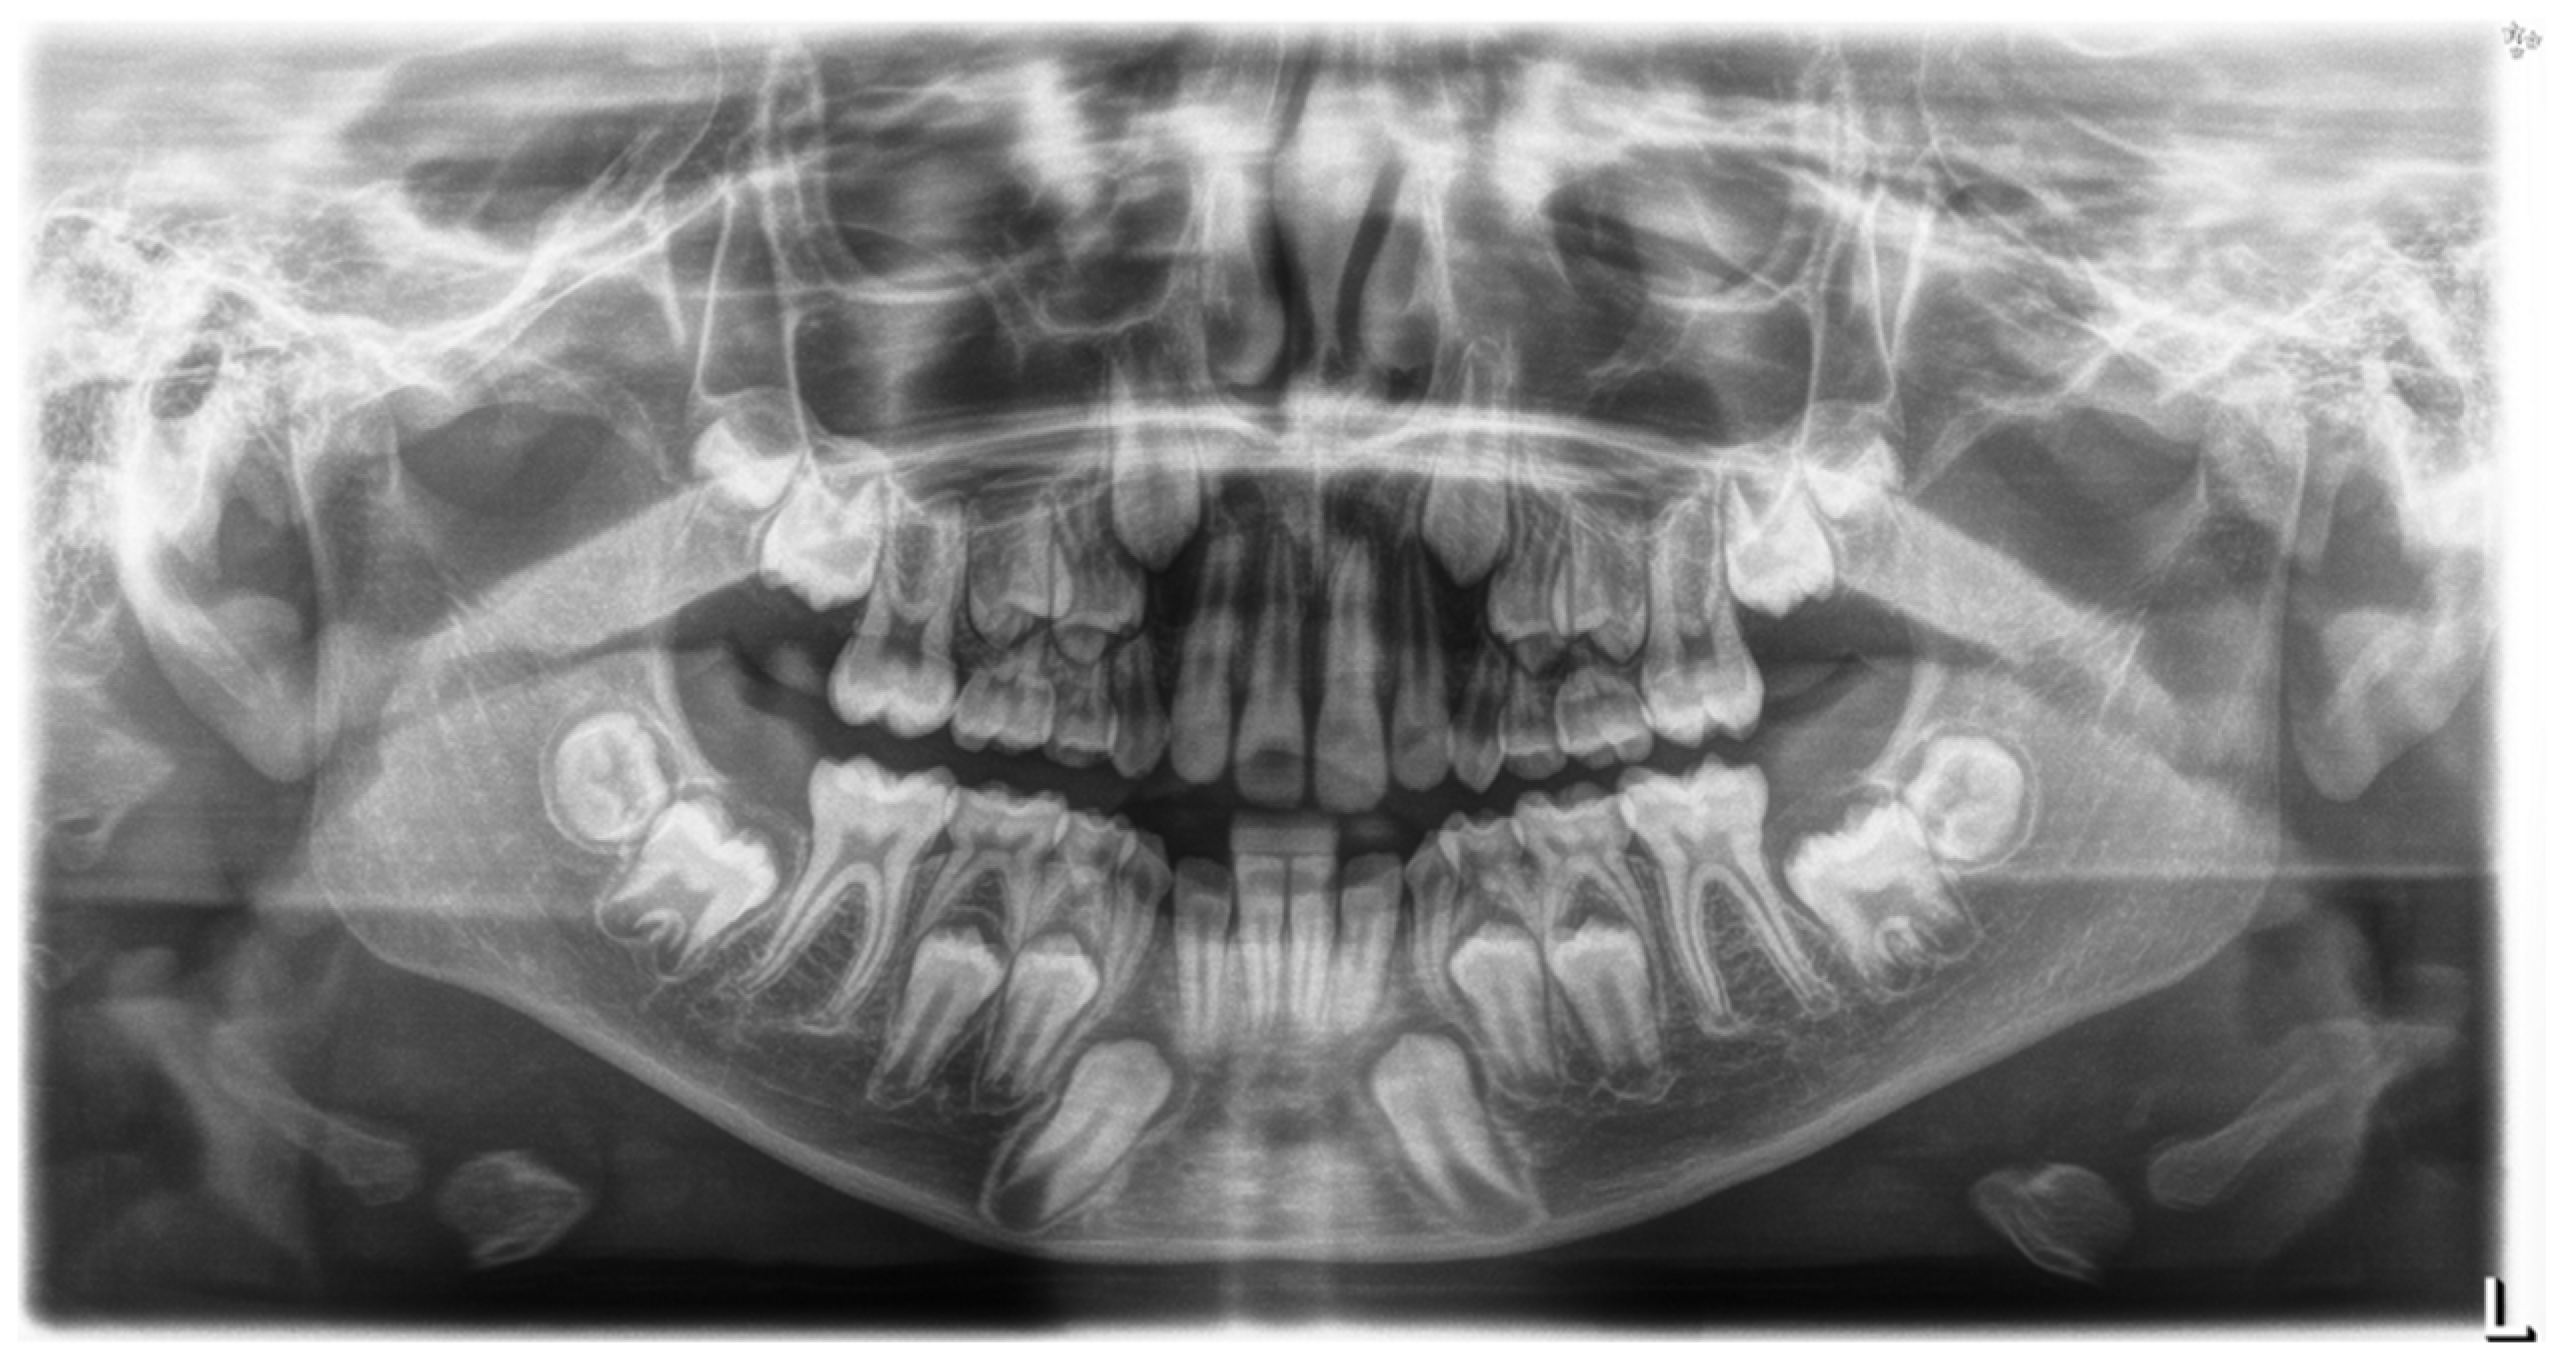

4. Case Report

4.1. Phase 1: Initial Orthodontic Treatment